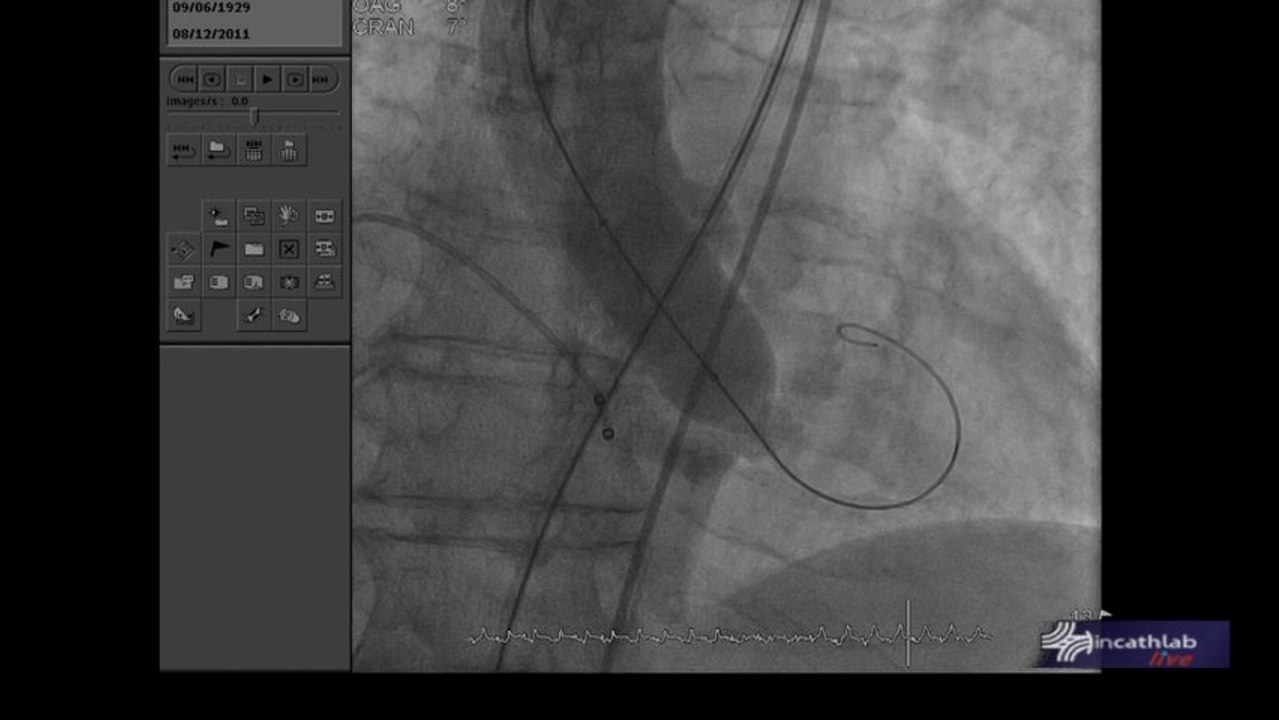

Live Case #9 : TAVI - Voie d'abord alternative

REVES 2019 - Dr Philippe Généreux, Dr Thomas Gandet & Dr Chadi Aludaat